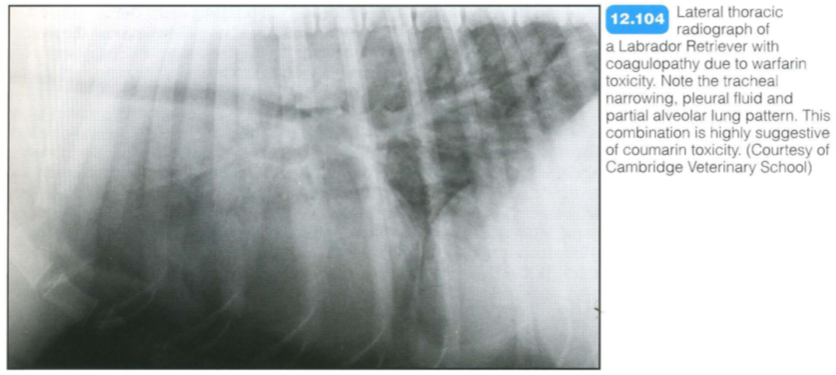

Most cases are associated with coagulopathies or trauma. Rodenticide poisoning (coumarin derivatives) is the most common cause of severe pulmonary haemorrhage; outdoor cats and dogs are at risk.

The combination of tracheal narrowing with pleural and mediastinal fluid and lung changes is suggestive of anticoagulant toxicity. Thoracic changes due to coumarin toxicity should resolve within 1-5 days of starting therapy. Haemorrhage due to Angiostrongylus vasorum infection usually also has radiographic changes of parasitic pneumonia. The pattern is classically peripheral in distribution.